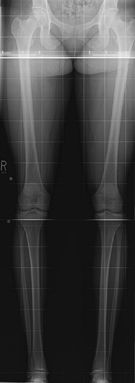

Leg Alignment—Include Joints from Hip to Ankle

Patient upright, equal weight in each foot. Both leg

alignment and leg length can be assessed on this study if

weight-bearing. The weight-bearing line passes from the middle of the

femoral head to the middle to the tibial plafond and should pass between

the tibial eminences. This determines varus or valgus deformity at the

knees. Used for pre- and postoperative assessment of total knee

arthroplasty.

![]() |

|

Figure 62 AP both legs.